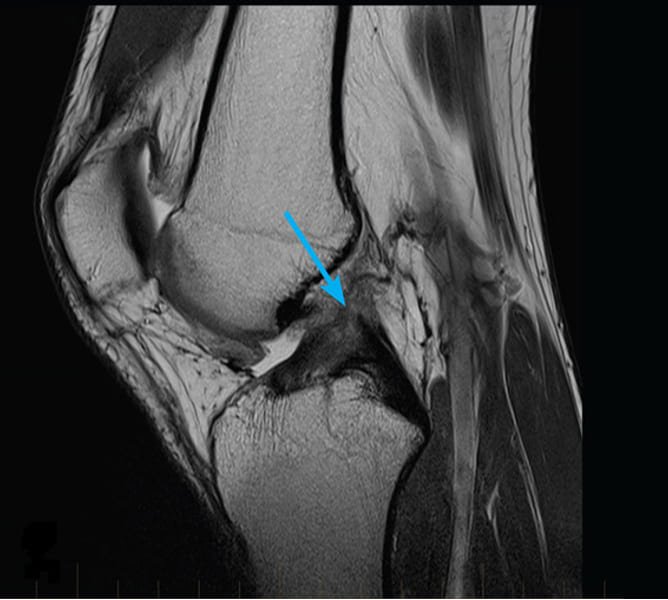

Podívejte se na tyto obrázky, můžete vidět, že na obrázku vpravo není žádný kloubní prostor, kosti se o sebe třou a způsobují silnou bolest. A tento proces je velmi těžké zastavit! Za pár let se ten člověk stane invalidním a už se nebude schopen sám živit.